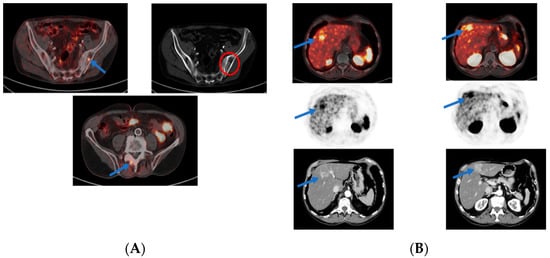

3.2. PSMA PET in Biochemical Recurrence PCa

3.3. Evaluation of PCa Patients for Possibility of PSMA Radioligand Therapies